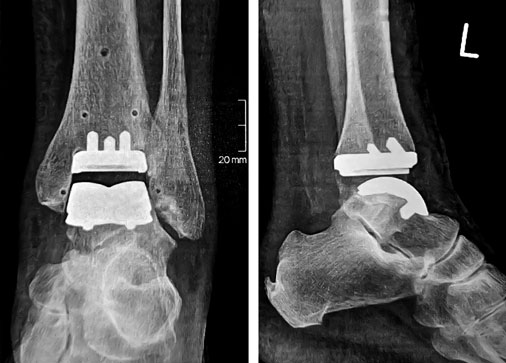

Patientin, 67 Jahre, 5 Monate nach operativer Versorgung mit Sprunggelenkimplantat